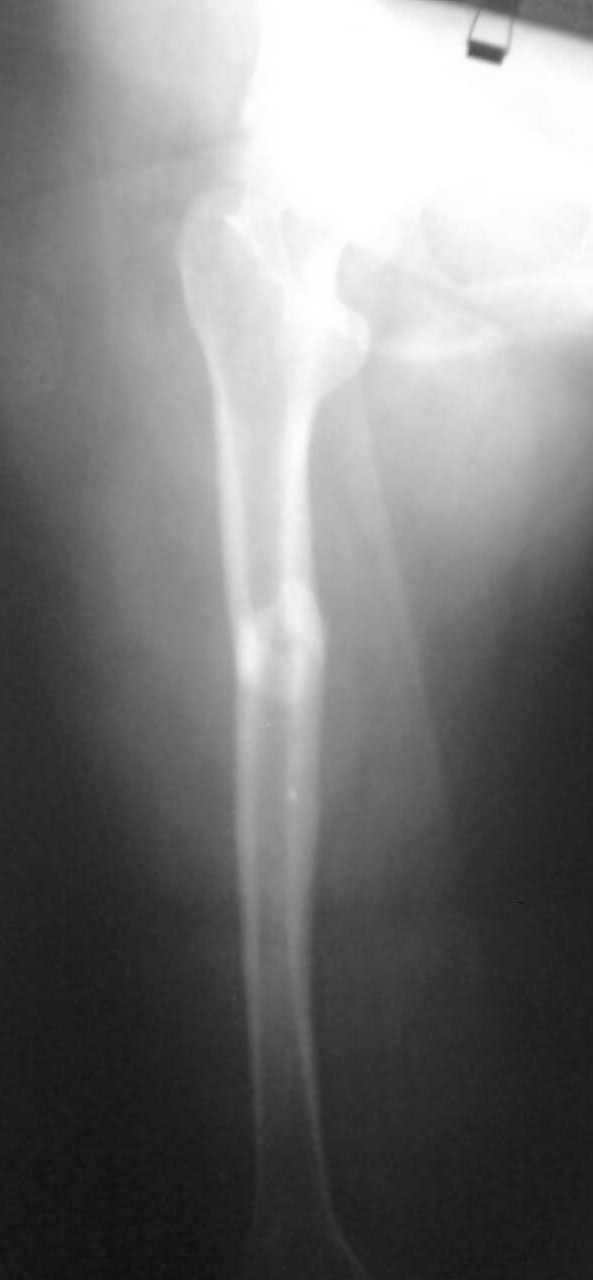

Немного добавьте подробностей pls - что за перелом? На снимке его толком не видно. Какие имплантаты доступны?

Перелом поперечный с незначительным смещением и с захождением отломков около 2,0см. Перелом типа А 1.